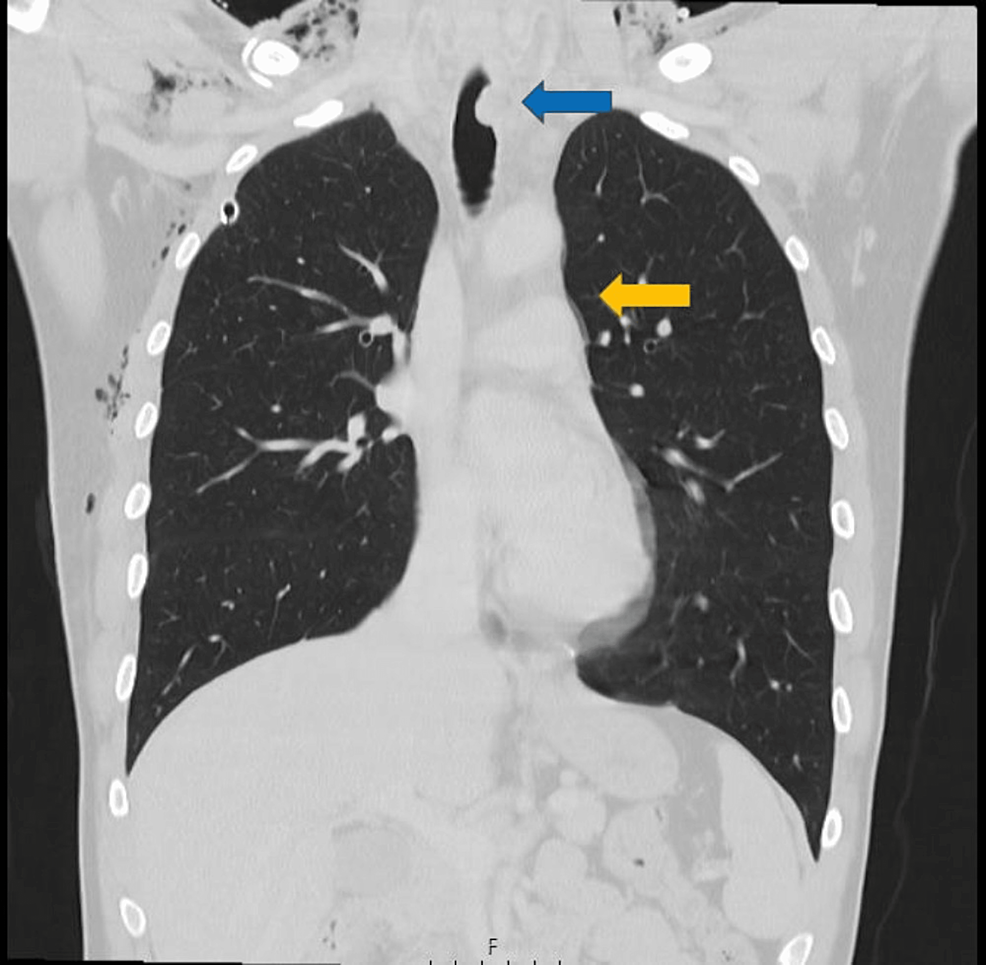

Thoracic CT showing posterior tracheal rupture (Arrow). Download Tracheal Rupture The major causes of tracheal injury include iatrogenic, blunt trauma, penetrating trauma, inhalation and aspiration of liquids or objects. Tracheobronchial tears are uncommon injuries or lacerations or puncture occurring anywhere in the tracheobronchial tree resulting from penetrating or blunt trauma to the neck or. Common etiologies include blunt or penetrating. A tracheal or bronchial rupture is a tear or break. Tracheal Rupture.